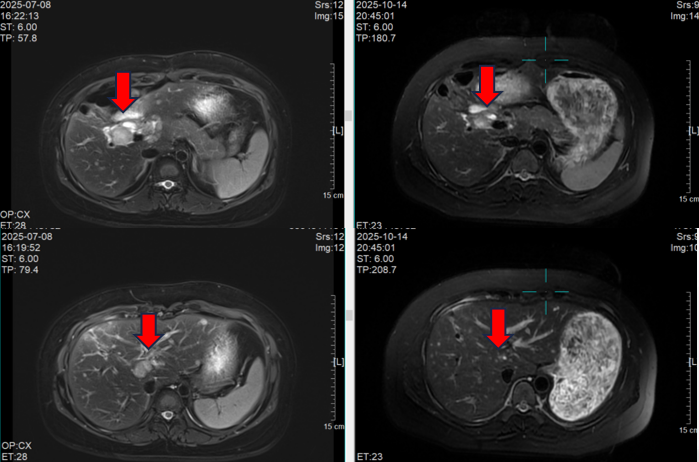

术后病理诊断为:胆囊浸润性癌,小细胞神经内分泌癌约80%,腺癌约20%;肿瘤突破胆囊壁并侵犯肝组织;脉管癌栓及神经侵犯;送检“13组淋巴结”1/5(腺癌)。免疫组化示小细胞成分Syn、CD56阳性,CgA部分阳性,Ki-67约80%;腺癌CK、CK7阳性;PD-L1 TPS < 1%。术后1个月复查MRI即提示肝术区及S5/S6段出现多发新发可疑转移灶。

患者术后接受一线EP化疗(依托泊苷 + 顺铂)5周期,疗效评估为疾病稳定(SD),PFS约6个月。2024转诊至我院。会诊病理提示小细胞神经内分泌癌成分比例进一步升高至约90%,腺癌成分约10%,周围肝组织可见转移灶(成分为小细胞神经内分泌癌),PD-L1 CPS=0,SSTR2阳性。患者拒绝再次肝穿刺活检。